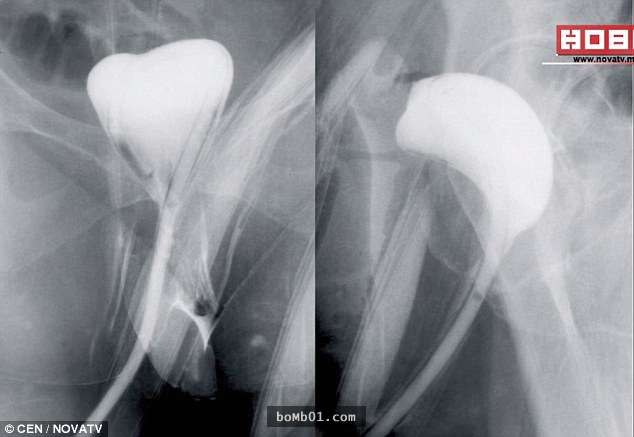

生病接受治疗时,患者很担心遇到庸医。马其顿斯科普里女子Jasminka Velkovska就遇到了这样的事。3年前她被检查出结肠癌,去医院做肿瘤切除手术,没想到手术完毕后癌症没治好,反而开始从阴道放屁。担忧的她忍不住去照X光,这才发现外科医生对自己做了超级过份的事。

▼Jasminka手术完成,处于恢复期时,医生问她有没有放屁,她回答有,但气体从阴道排出。

▼医生说这没有问题,她很快就会好起来,但Jasminka非常害怕,最后还是照了X光,这才发现她的结肠竟与阴道连接起来。不仅如此,医生根本没有切除她结肠内的肿瘤,手术完全出错了。

▼她只能再次接受手术切除肿瘤,这次她换了一间医院,终于没有再发生类似的事。